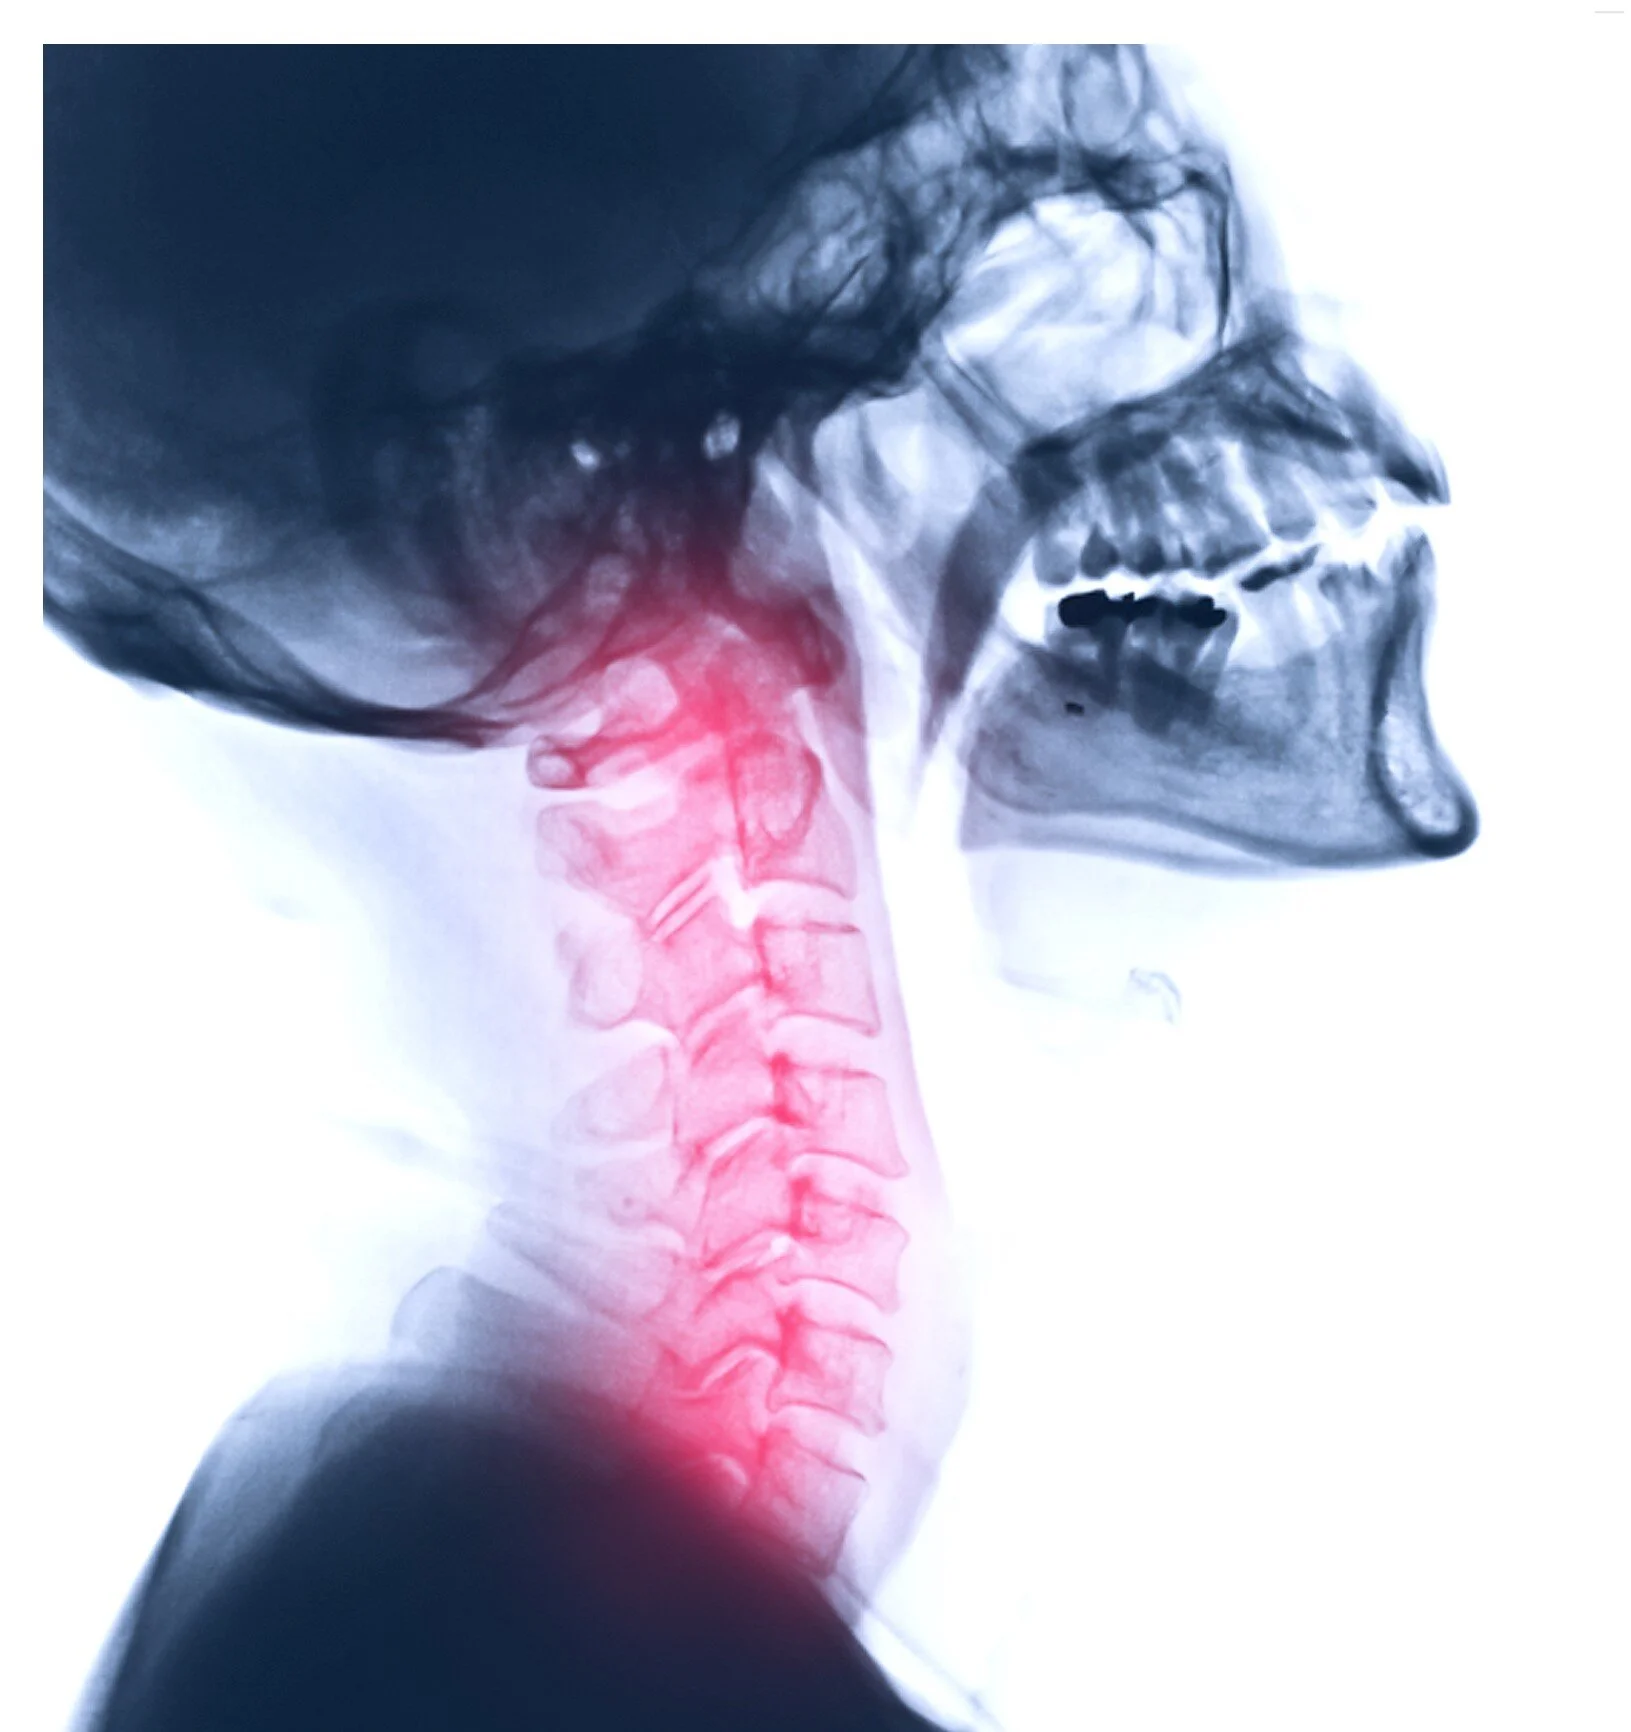

Here’s our review of a new (ish) paper, showing more effective variations on common exercises for restoring the cervical lordosis and stressing the importance of doing so.. It’s a shame we aren’t seeing more work in this area by chiropractors but still, our summary is a quick read and well worth the time for anyone serious about creating better spinal corrections.